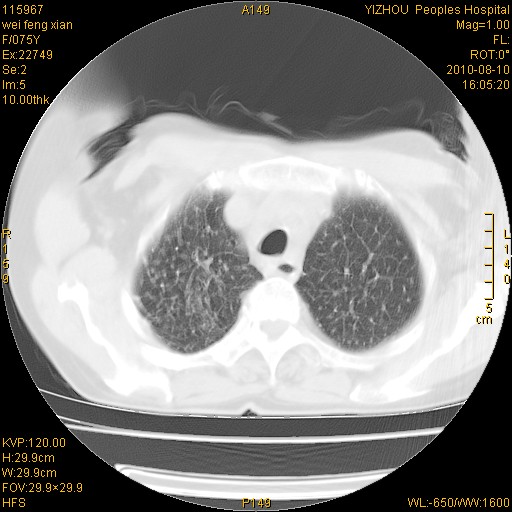

标题: CT28313:两肺弥漫性病变 [打印本页]

标题: CT28313:两肺弥漫性病变

女,75岁,患者反复头昏乏力面色苍白3年,再发10天入院。临床贫血查因。

双肺间质增生并右肺上叶炎性改变,不除外右肺上叶结核病肺内播散

考虑右肺上叶炎症合并双肺结核可能性大,建议上传纵隔窗ct图片。

双肺结核可能性大

考虑尘肺并结核;右上肺支气管扩张!

结核、尘肺、支气管肺泡癌都不能除外

右肺上叶继发性肺结核伴肺内血型播散!

考虑右肺上叶继发性肺结核伴两肺播散。